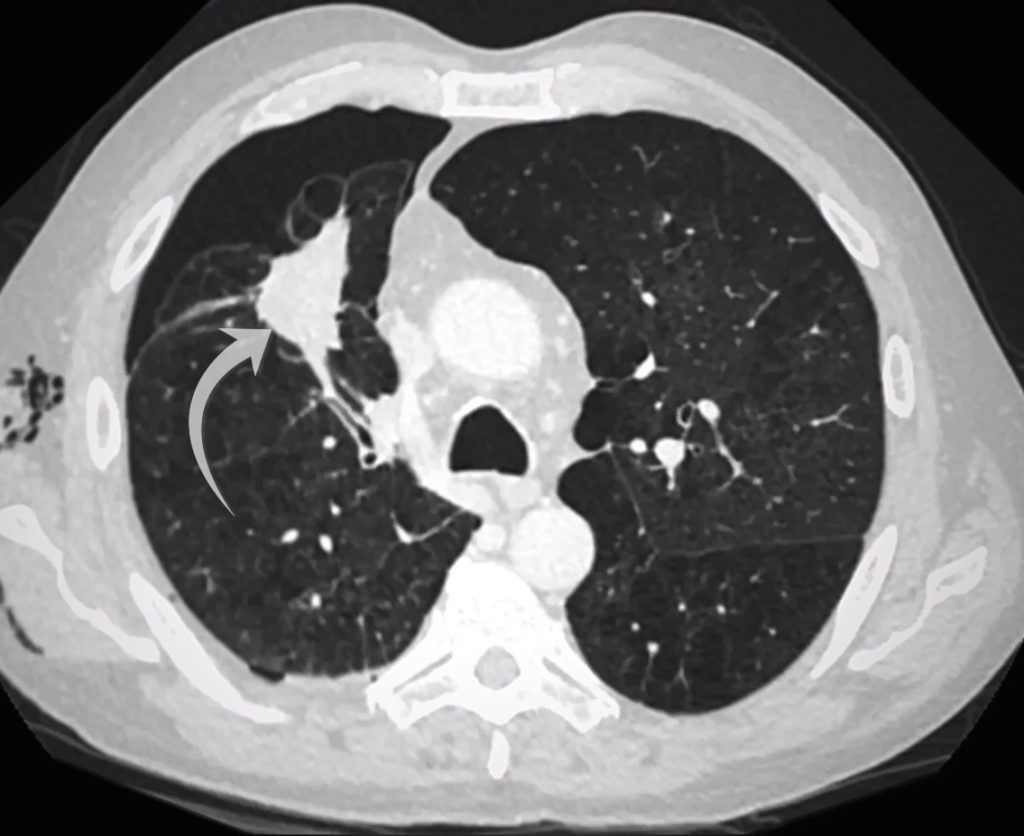

CT confirms a right upper lobe opacity accounting for the right mid zone opacity on chest X-Ray.

A right lower lobe opacity accounts for the opacity seen overlying the right hilum on chest X-Ray.

Examining the right upper lobe lesion in more detail, we see small spicules radiating from it. A spiculated lesion raises concern for a primary lung cancer. In my experience however you need to adopt a little caution when the underlying lung is abnormal as with severe emphysema a lot of lesions can look spiculated!

The right upper lobe lesion is spiculated.